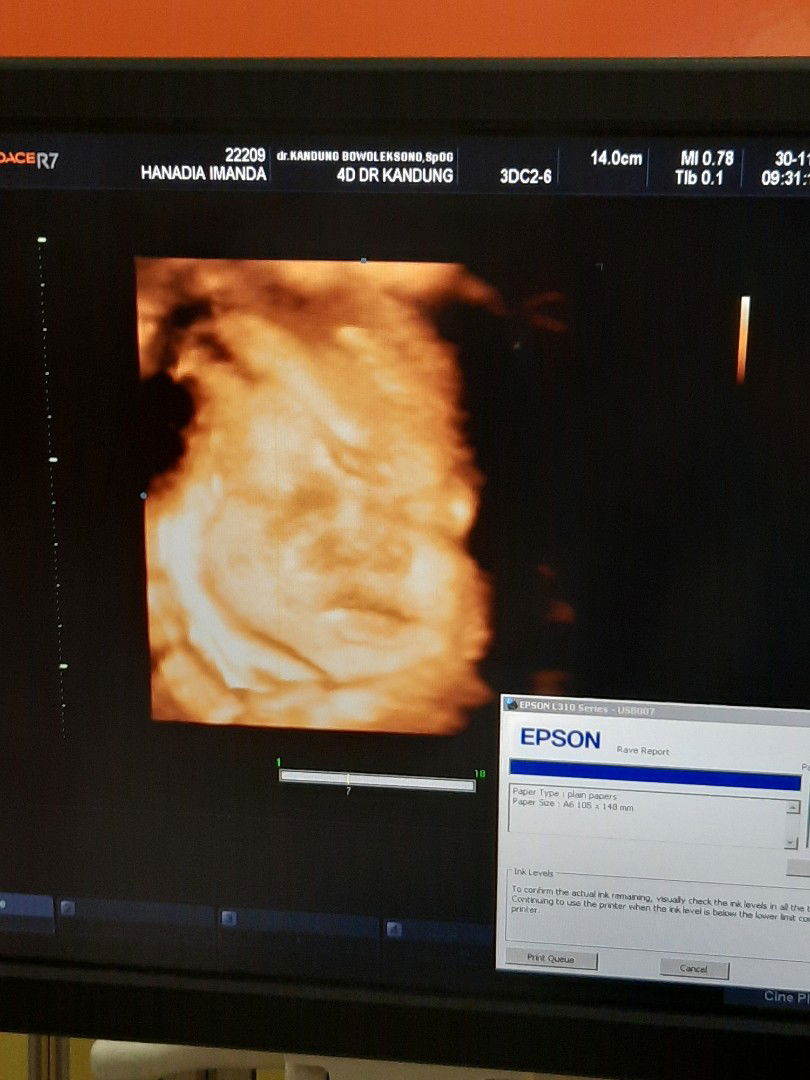

35 weeks

Senengnya td bisa liat baby di dalem perut senyum meskipun tangannya yg satu nutupin mata ? sehat2 yaa sayang, sampai ketemu bulan januari ?